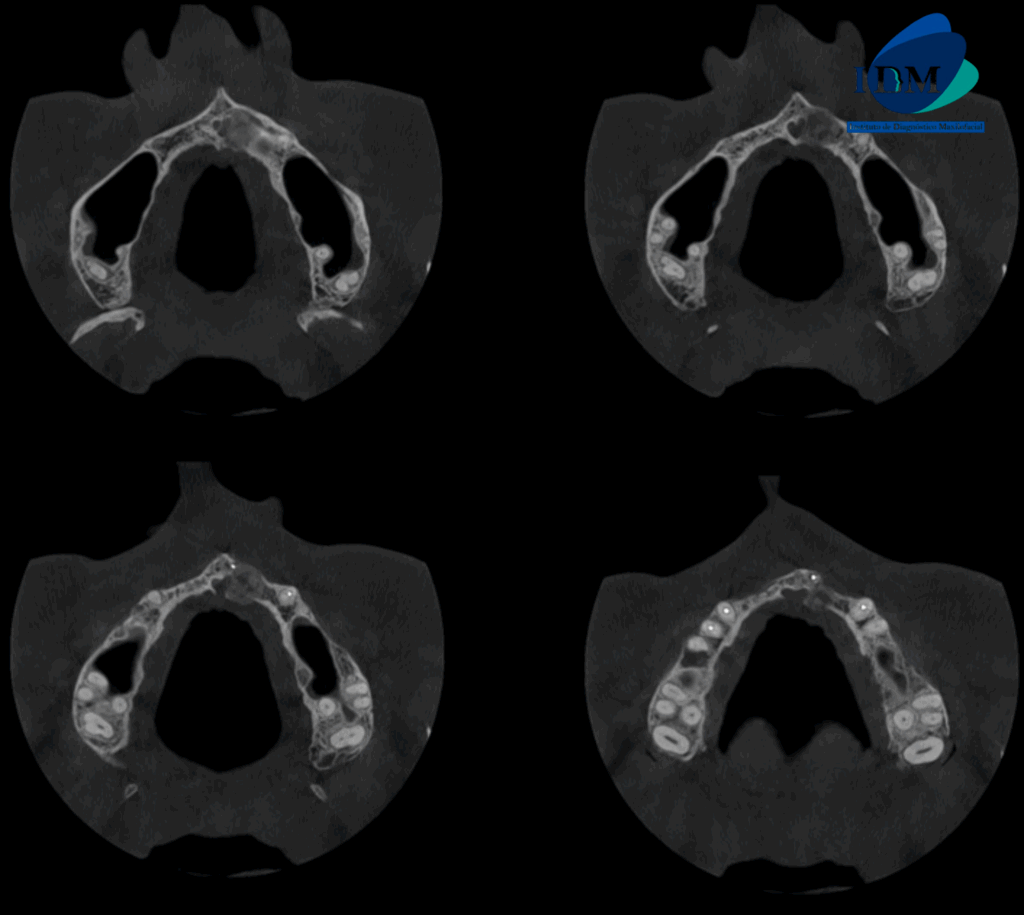

En la radiografía panorámica (Figura 1), se aprecia piezas dentarias con material de obturación, además se evidencia imagen radiopaca definida a nivel apical de pieza 21.

Radiografia Panorámica